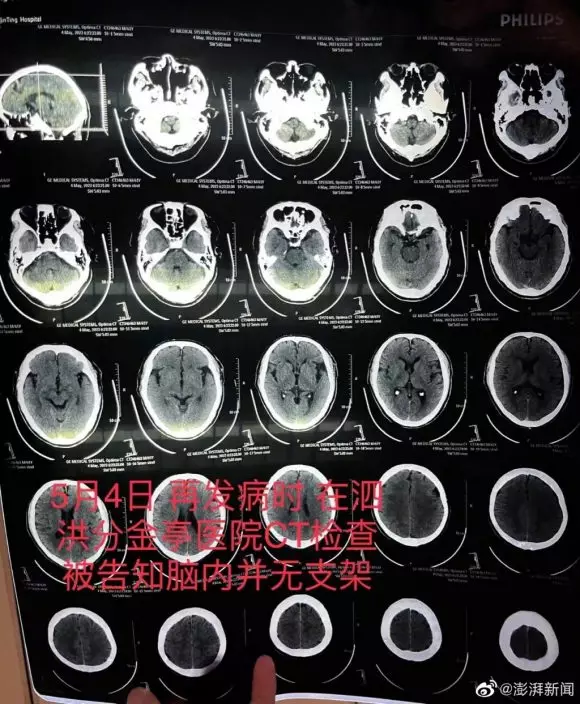

老翁病發入院檢查發現根本沒有裝血管支架。

到了5月4日,朱老翁突發嚴重腦梗,被救護車送至江蘇省宿遷市泗洪縣分金亭醫院搶救,CT檢查竟發現其顱內段部分動脈已嚴重堵閉,同時未有植入支架。朱先生無法接受,以為是小醫院檢查不出來,決定轉回宿遷市第一人民醫院,此時主刀醫生齊某才承認,之前植入支架失敗。